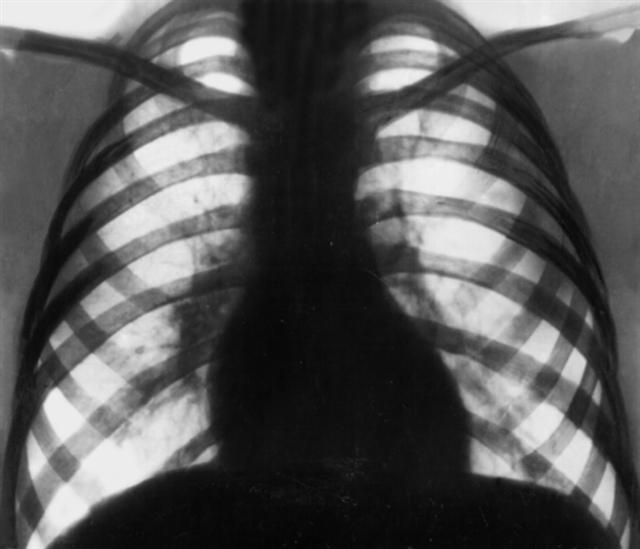

Рис. 3 а). Рентгенограмма в прямой проекции органов грудной клетки при туберкулезе внутригрудных лимфатических узлов: тень корня правого легкого расширена и уплотнена за счет увеличенных лимфатических узлов.